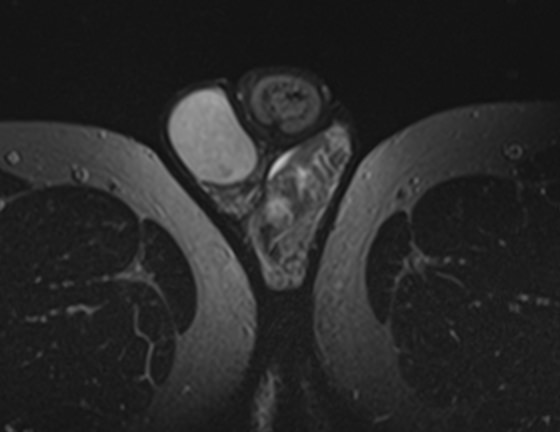

Метод позволяет диагностировать патологию мужских половых желез (яичек), их придатков и семявыносящих протоков. Эти органы, вместе с кровеносными сосудами, лимфатическими протоками и нервами, располагаются в мошонке – мешотчатом образовании из гладких мышц и кожи.

Во время исследования производится послойное сканирование в трех взаимно перпендикулярных плоскостях с шагом от 1 мм, в дальнейшем с помощью инновационных приложений аппарат трансформирует полученные данные в трехмерные изображения. Методика позволяет выявлять структурные изменения органов мошонки на самой начальной стадии. Особенно это важно для диагностики опухолей.

При подозрении на развитие объемных образований, для проведения дифференциальной диагностики, может применяться контрастное усиление. В таких случаях, пациенту внутривенно вводится контрастный препарат, содержащий гадодиамид (соли металла гадолиния), который способен «высвечивать» патологические очаги при попадании в зону действия магнитного поля томографа. С помощью контрастирования удается выявлять опухоли размером от 1 мм. Ранняя диагностика онкозаболеваний позволяет вовремя назначить необходимое лечение.

После того, как исследование окончено, задачей врача является расшифровка полученных снимков. Чаще всего удается определить следующие патологические процессы:

• Аномалии строения органа;

• Злокачественные или доброкачественные новообразования;

• Фиброзные изменения кавернозных тел;

• Сосудистые патологии, в том числе варикоцеле;

• Водянка яичка;

• Наличие абсцесса;

• Пневматоз;

• Склероз яичек;

• Крипторхизм;

• Воспалительные процессы;

• Аденомиоз;